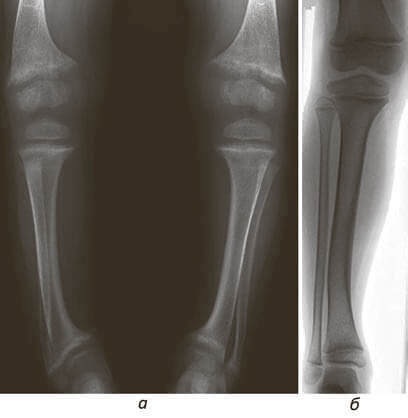

а. Посмотрите на дистальные отделы бедренных и большеберцовых костей – отметьте их отклонение кнутри и неравномерную плотность кости

б. Через год после начала лечения рахита форма и структура кости значимо улучшилась.